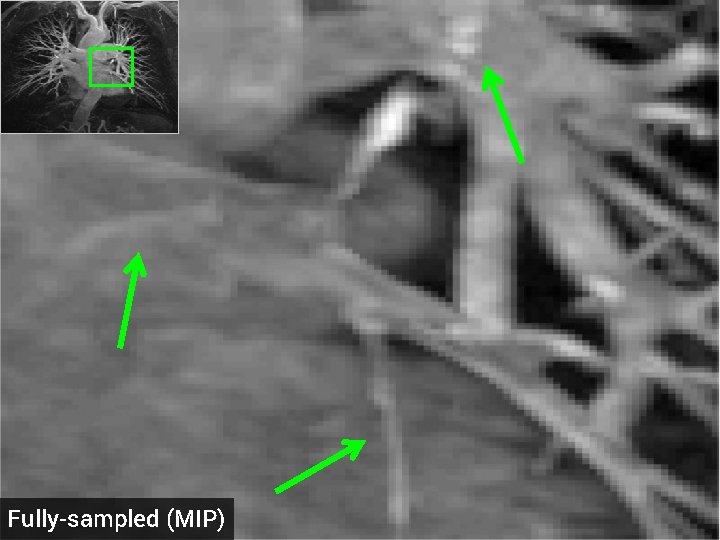

Total Variation (TV) penalty for CS-MRI § Promotes recons with sparse gradient <-> piecewise constant regions § Advantages: fast algorithms, easy to implement § Disadvantages: loss of detail at high accelerations § Ex: 3 -D MRA dataset, 5 -fold acceleration, random k-space samples Fully-sampled (MIP) TV recon, 5 x accel. , SNR = 13. 87 d. B

Fully-sampled (MIP)

Proposed method, 5 x accel. (MIP) SNR = 14. 23 d. B